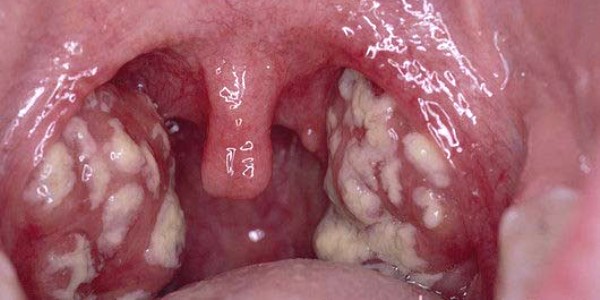

Фолликулярная: характеризуется наличием гнойного воспаления лимфоидных образований глотки (фолликулов) в виде отдельных очагов нагноения на небных, трубных, глоточных или язычных миндалинах, а также увеличенных шейных регионарных лимфоузлов.

Заболевание сопровождается резким повышением температурных показателей, болью в горле, слабостью. Ребенок становится беспокойным, плачет, отказывается от еды, не хочет ничего делать. Можно наблюдать затруднение речи, наличие серого налета на языке;

Лакунарная: проявляется стремительно, характеризуется недомоганием и слабостью, повышением температуры тела до 39 градусов, ознобом, нарушением сна, потерей аппетита, уменьшением активности, неприятными ощущениями в гортани.

Симптомы ангины у детей: воспаление и увеличение лимфоузлов, отек горла, наличие гнойных образований белого или желтого цвета на миндалинах, либо полного покрытия налетом поверхности (одной или обеих миндалин);